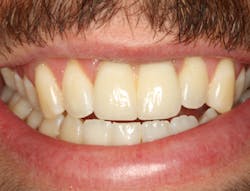

The same arguments have been advanced for not splinting adjacent implants in segmental reconstructions (figure 1). Plaque-related peri-implantitis is the most common biological complication in implant dentistry. A passive fit of prostheses on their supporting implants is considered essential for minimizing mechanical and biological overloading. On the other hand, it is also claimed that splinting can prevent overloading (figure 2). Screw loosening and fracture of veneering material are the most common mechanical complications of loading, although there is little evidence that it results in loss of integration.

Figure 1: Nonsplinted adjacent implants